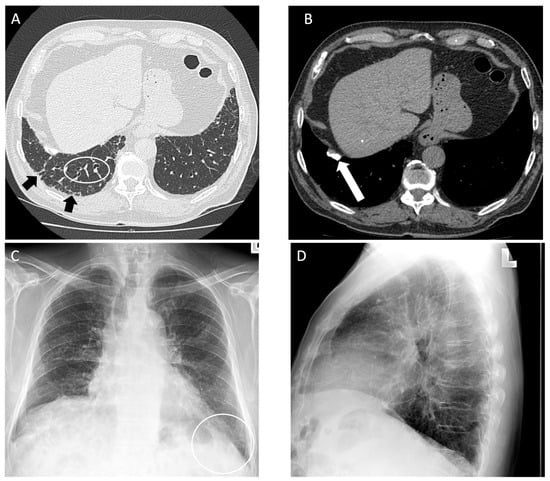

Figure 3.

An 83-year-old male with 75 pack year smoking history and asbestos exposure from construction work, diagnosed with asbestosis. (A) Axial computed tomography image demonstrates subpleural reticulation (black arrows) and mild traction bronchiectasis (white circle) of right lung in keeping with mild asbestosis; (B) mediastinal windows demonstrate a calcified pleural plaque along the right diaphragm (white arrow); (C) posteroanterior and (D) lateral chest radiograph demonstrate mild reticular markings in the basal lung consistent with mild fibrosis, best appreciated in the left lateral costophrenic angle (white circle).